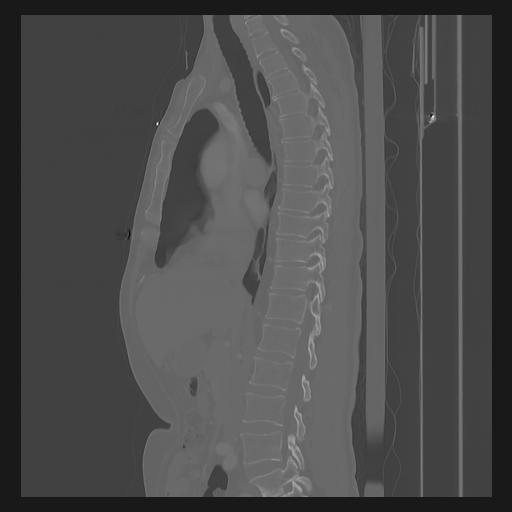

33 PULMON,CE,Sagittal,3.000,PULMON,Sagittal,